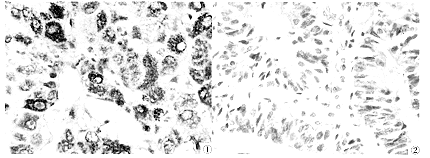

子宫内膜癌P16表达的免疫组织化学观察

随机选取本院1980~1990年间60岁以上、临床及随访资料完整的子宫内膜癌手术切除病例67例 ......